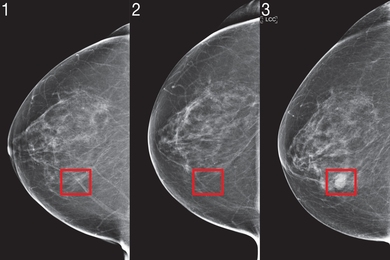

Dr. Larry Norton i Qendrës së Gjirit Lauder shpjegoi për CNN se ‘AI’, e cila ka ekzistuar që nga fundi i viteve 1990, po bëhet më e dobishme në identifikimin e problemeve të mundshme shëndetësore. AI mund të ndihmojë radiologët duke identifikuar zonat në mamografi që kanë nevojë për ekzaminim më të afërt.

Sidoqoftë, AI ka për qëllim të ndihmojë, jo të zëvendësojë, profesionistët e mjekësisë njerëzore. Mund të zvogëlojë ngarkesën e punës së radiologëve me 30% dhe të rrisë shkallët e zbulimit të kancerit me 13%, sipas New York Times. AI është përdorur gjithashtu me sukses për të zbuluar kancerin e mushkërive.